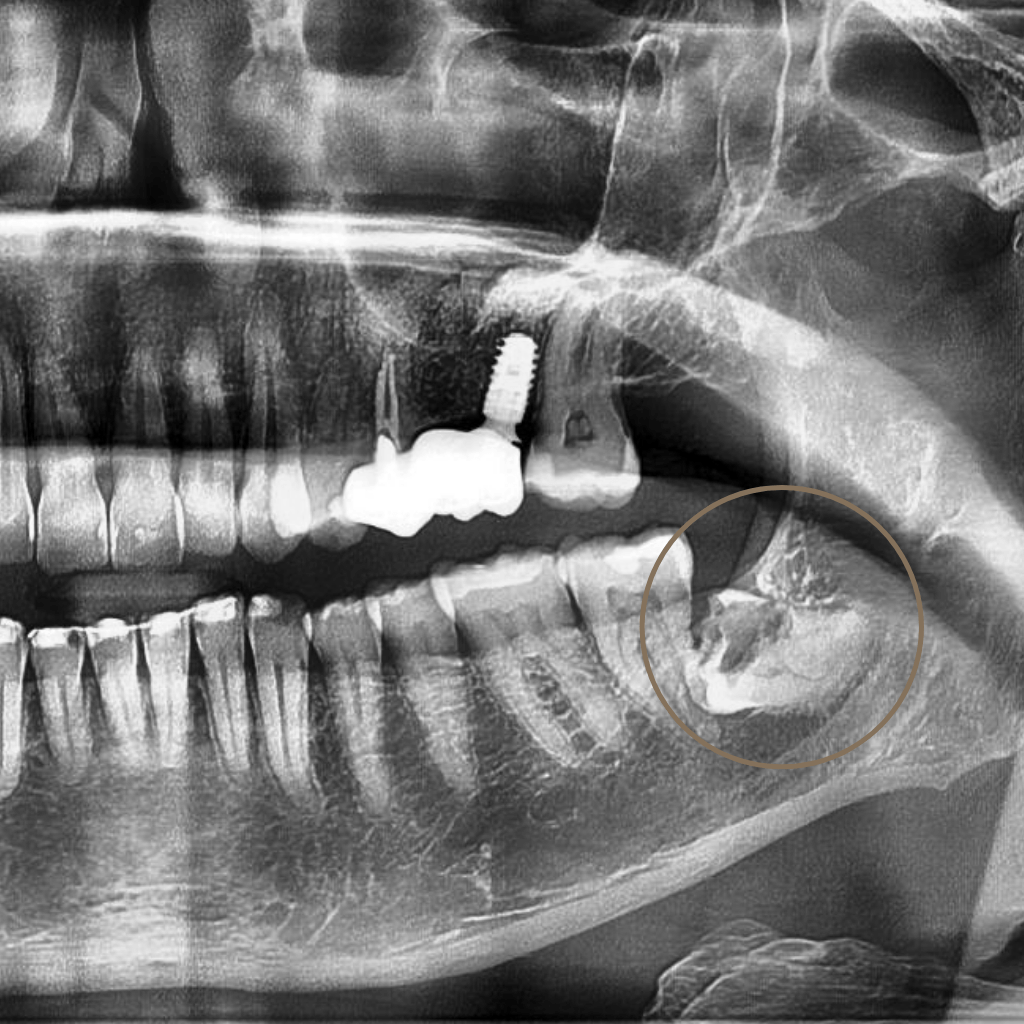

Екстракцията е хирургична процедура, при която зъбът се отстранява, когато неговото запазване не е възможно или би компрометирало цялостното орално здраве. В Aesthetico екстракциите се извършват след внимателна оценка и с ясна цел – лечение, облекчаване на болката и създаване на стабилна основа за последващи стъпки.